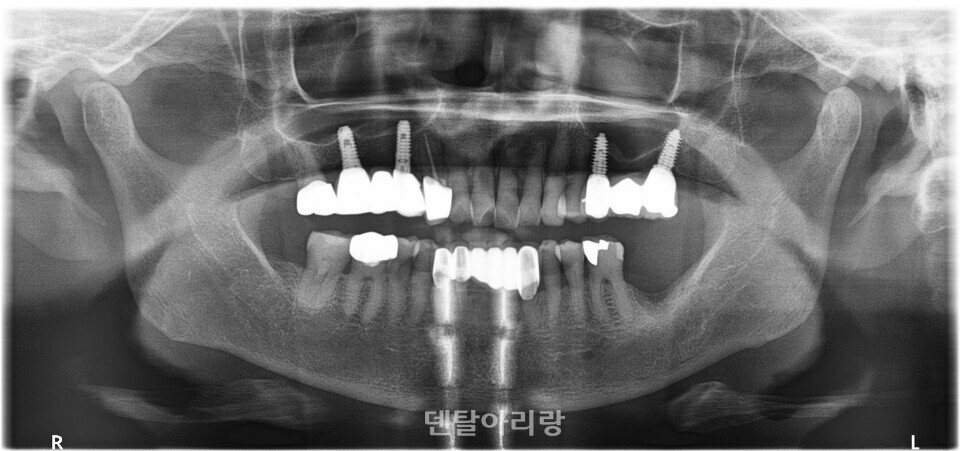

상악동 골이식술 시, 해부학적으로 고려해야 할 요소 중 또다른 하나는 상악동 중격(septum)이다<그림 10>.

△그림 10. 상악동내 중격의 컴퓨터 영상장치 이미지

대부분의 경우에서 상악동 아래 바닥에 중격이 존재하나 그 양상은 매우 다양하다. 상악동의 중격은 바닥벽 뒤쪽 치아뿌리 사이에 주로 나타나며, 1~2%의 경우에 완전하게 분리되어 나뉘어 작은 덧굴(Haller’s cells)을 이루기도 한다.

상악골의 중격은 치아가 있을 때에는 교합력을 분산시키는 역할을 하지만, 나이가 들어 치아가 빠지면서 중격도 점차 없어지기도 한다. 이러한 시상뼈중격(sagittal bony septa)은 평균 2mm의 두께를 가지며, 모양이 매우 다양하다. 상악 구치부 발치시에 치아뿌리의 부서진 조각이 상악동 안으로 들어가 중격에 의해 생긴 오목한 부위에 머무는 경우 이를 제거하는 데 어려움이 생길 수 있으며, 상악동 염증 시 고름(pus)의 배출을 방해할 수도 있다. 또한 임플란트 식립을 위한 상악동 점막 거상술 시, 점막의 찢어짐을 일으킬 수 있어 특히 주의해야 한다. 이를 예방하기 위해 술전 방사선 영상 진단을 통해 중격의 위치와 형태를 진단하고 상악동 측벽 접근법을 시행할 때, 상악동 중격을 중심으로 좌, 우로 나뉘는 2개의 골창을 형성하여 골이식을 시행하는 것이 추천된다<그림 11>.